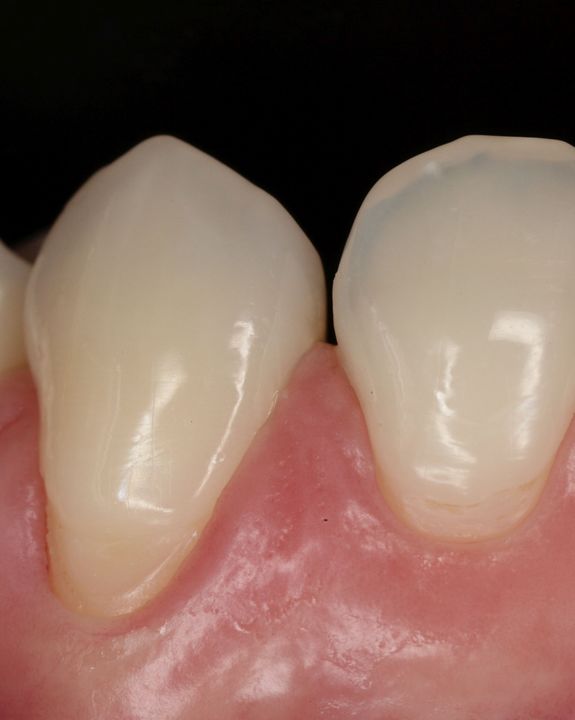

La microchirurgia plastica parodontale è utilizzata per arrestare la progressione di malattie parodontali e delle recessioni gengivali (retrazione delle gengive), ma anche per migliorare l’aspetto estetico della linea gengivale e del sorriso.

Radici dentali esposte sono il risultato della recessione gengivale. I denti in questi casi spesso sono sensibili a cibi e liquidi caldi, freddi o acidi. Le cause per cui si hanno recessioni gengivali sono le stessa da cui originano le parodontiti, prime tra tutte placca batterica, scarsa igiene orale, traumatismi, fumo. Esistono poi una varietà di fattori predisponenti che dovrebbero essere individuati per limitarne l’azione distruttiva e per prevenire l’ulteriore perdita di gengiva ed osso.

Innesti di tessuto molle possono essere utilizzati per coprire le radici esposte ma anche per ricostruire il tessuto che è andato perso. Il tessuto molle viene prelevato dal palato o da altre zone intraorali. L’intervento è quasi indolore e non esistono possibilità di rigetti. Il tessuto prelevato dalla zona donatrice si riforma spontaneamente in poche settimane.

Numerosi benefici derivano dalla chirurgia plastica parodontale: l’innesto di tessuto molle ricostruisce il tessuto perso e previene l’ulteriore progressione della recessione gengivale e dell’osso alveolare. Gli innesti gengivali riducono la sensibilità del dente e prevengono la formazione delle carie alle radici. E soprattutto migliorano l’aspetto estetico della linea gengivale e quindi del sorriso di ogni paziente.